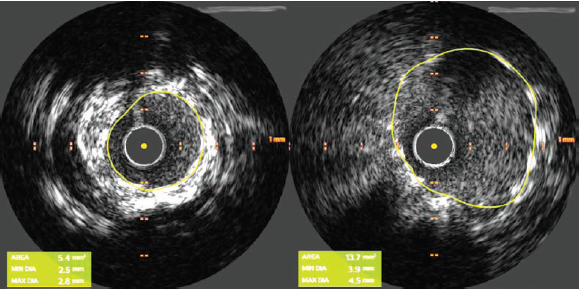

Given the fibrocalcific disease visualized on IVUS, we performed plaque modification with a 3.5 x 15 mm Wolverine cutting balloon (Boston Scientific) with several inflations from the mid LAD to the ostium of the LMCA. IVUS re-assessment demonstrated calcium fracture, indicating the lesion was adequately prepared to accommodate a stent (Figure 4).

We then deployed a 4.0 mm x 24 mm Synergy Megatron stent (Boston Scientific) covering the ostium of the LMCA to the proximal LAD. The mid LAD was treated with 2.75 mm x 15 mm Resolute Onyx stent (Medtronic) deployed just distal to the take-off of the first diagonal branch, with a good final result (Figure 5). Post-stent IVUS demonstrated a minimal stent area of 5.4 mm2 within the mid-LAD stent and 13.7 mm2 within the LMCA (Figure 6).